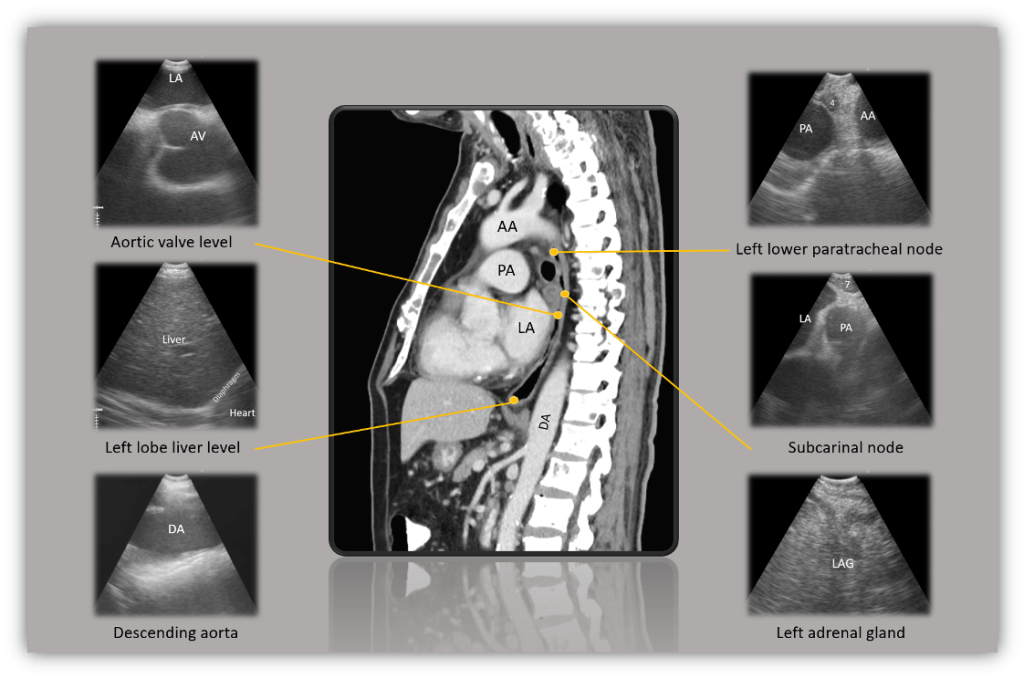

เนื่องจากการทำ EUS-B เป็นหัตถการที่ยังมีที่ใช้ไม่มากในประเทศไทยด้วยข้อจำกัดในเรื่องของอุปกรณ์และผู้เชี่ยวชาญที่มีประสบการณ์มากพอในการทำหัตถการเนื่องจากต้องใช้ระยะเวลาการเรียนรู้ยาวนาน (long learning curve) ทำให้ในแต่ละสถาบันทั่วโลกมีเทคนิคและกระบวนการในการทำ EUS-B ที่แตกต่างกันออกไปบ้าง ส่งผลให้ระบบการสอนยังไม่เป็นมาตรฐานเดียวกัน จนกระทั่งในปี พ.ศ. 2555 Konge และคณะ33 ได้กำหนดแนวทางขั้นตอนในการทำ EUS (EUS assessment tool, EUSAT) เพื่อหาระยะของมะเร็งปอดไว้เพื่อให้เป็นมาตรฐานในการประเมินทักษะในการทำ EUS อย่างเป็นระบบ โดยกำหนดจุดอ้างอิงทางอัลตราซาวด์ที่ต้องระบุจำนวน 6 ตำแหน่ง ได้แก่ left lobe liver, aorta และ celiac trunk, left adrenal gland, lymph node at station 7, 4L,และ 4R ตามลำดับ การศึกษาที่เกี่ยวข้องกับการทำ EUS-B ต่อมาจึงมักอ้างอิงกระบวนการของ EUSAT มาเป็นหลักในวิธีการทำหัตถการของการวิจัย อย่างไรก็ตามจุดอ้างอิงและวิธีขั้นตอนในการทำในแต่ละสถาบันก็อาจจะยังมีความแตกต่างกันไปด้วยเหตุผลที่กล่าวไปแล้ว บางสถาบันอาจจะใช้ Left atrium หรือ aortic valve level เป็นจุดอ้างอิงเริ่มต้นของการทำ EUS-B ก็มี ทั้งนี้ขึ้นกับความถนัดและการฝึกตั้งแต่เริ่มต้นของแต่ละที่

- Left atrium and aortic valve level: จากตำแหน่งของ ต่อมหมวกไตข้างซ้ายปรับกล้องกลับมาสู่ neutral position และถอยกล้องขึ้นมาจนเริ่มเห็นส่วนของหัวใจ ที่ตำแหน่งนี้เหนือกระบังลมหากหมุนกล้องไปทางด้านหลังของผู้ป่วยจะเป็นตำแหน่งของต่อมน้ำเหลืองสถานี paraesophageal node (8) เมื่อเห็นหัวใจแล้ว ถอยกล้องขึ้นมาจนพบกับ aortic valve ในตำแหน่งด้านใต้ left atrium (LA) ที่อยู่ด้านบน valve ติดกับผนังหลอดอาหารอีกที ในตำแหน่งนี้แนะนำว่าควรปรับความลึกของอัลตราซาวด์ (depth) ไว้ที่ประมาณ 6-9 เซนติเมตร จะทำให้สามารถมองหา aortic valve ที่อยู่ลึกลงไปได้ง่ายขึ้น

- Subcarinal node: ต่อมน้ำเหลือง subcarinal (7) นั้นอยู่บริเวณระหว่าง LA และ pulmonary artery (PA) หลังจากที่เห็น LA แล้ว ให้ถอยกล้องขึ้นมาจนถึงบริเวณเหนือ LA ซึ่งจะเห็น PA อยู่ทางด้านขวาของภาพตามรูป ในกรณีที่ไม่เห็นต่อมน้ำเหลืองบริเวณดังกล่าวอย่างชัดเจน ควรปรับความลึกของอัลตราซาวด์เป็น 4 เซนติเมตร เพื่อค้นหาต่อมน้ำเหลืองอย่างละเอียดต่อไป

- Left lower paratracheal node: ต่อมน้ำเหลือง left lower paratracheal (4L) จะอยู่ที่ตำแหน่งของ aortopulmonary window เหมือนกับที่เห็นในภาพของ EBUS กล่าวคือจะเห็น aortic arch อยู่ทางด้านขวาและ PA อยู่ทางด้านซ้ายของภาพ โดยเริ่มจากตำแหน่งของ subcarinal node (7) แล้วถอยกล้องออกมาเล็กน้อยจน PA เลื่อนมาอยู่ฝั่งซ้ายของภาพแล้วหมุนกล้องทวนเข็มนาฬิกาจนพบตำแหน่งของ AP window ซึ่งเป็นตำแหน่งของ left paratracheal node นั่นเอง

รูปที่ 2. แสดงตำแหน่งอ้างอิงที่สำคัญบน EUS-B (LA = Left atrium, AV = Aortic valve, AA = Aortic arch, PA = Pulmonary artery, DA = Descending aorta, LAG = Left adrenal gland)